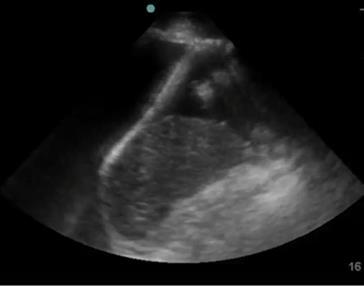

Bild: Lunge, Pleuraerguss mit invers gewölbtem Zwerchfell